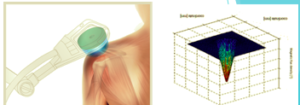

- Sappiamo benissimo che FARADY dimostrò che variando il flusso del campo magnetico in un circuito si generava una differenza di potenziale ovvero una CORRENTE INDOTTA

- Lo stesso succede al corpo umano, se colpito da un campo magnetico, nel corpo si inducono delle correnti con direzione perpendicolare a quella di andamento del campo magnetico

- L’intensità della corrente indotta e di conseguenza gli effetti, sono direttamente proporzionali all’intensità del campo magnetico. Forte intensità del campo, elevate correnti indotte